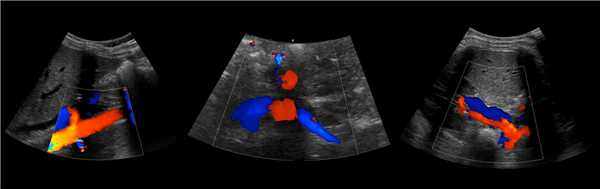

Рисунок. В режиме ЦДК на продольном (1) и поперечном (2) срезах от аорты отходят ППА и ЛПА. Сосуды направляются к воротам почки. Кпереди от почечной артерии располагается почечная вена (3).

Рисунок. Почечные вены впадают в нижнюю полую вену (1, 2). Аортомезентериальный «пинцет» может сдавливать ЛПВ (3).

Рисунок. В норме при ЦДК сосуды почек прослеживаются до капсулы (1, 2, 3). Главная почечная артерия входит через ворота почки, добавочные артерии из аорты или подвздошной артерии могут подходить у полюсов (2).